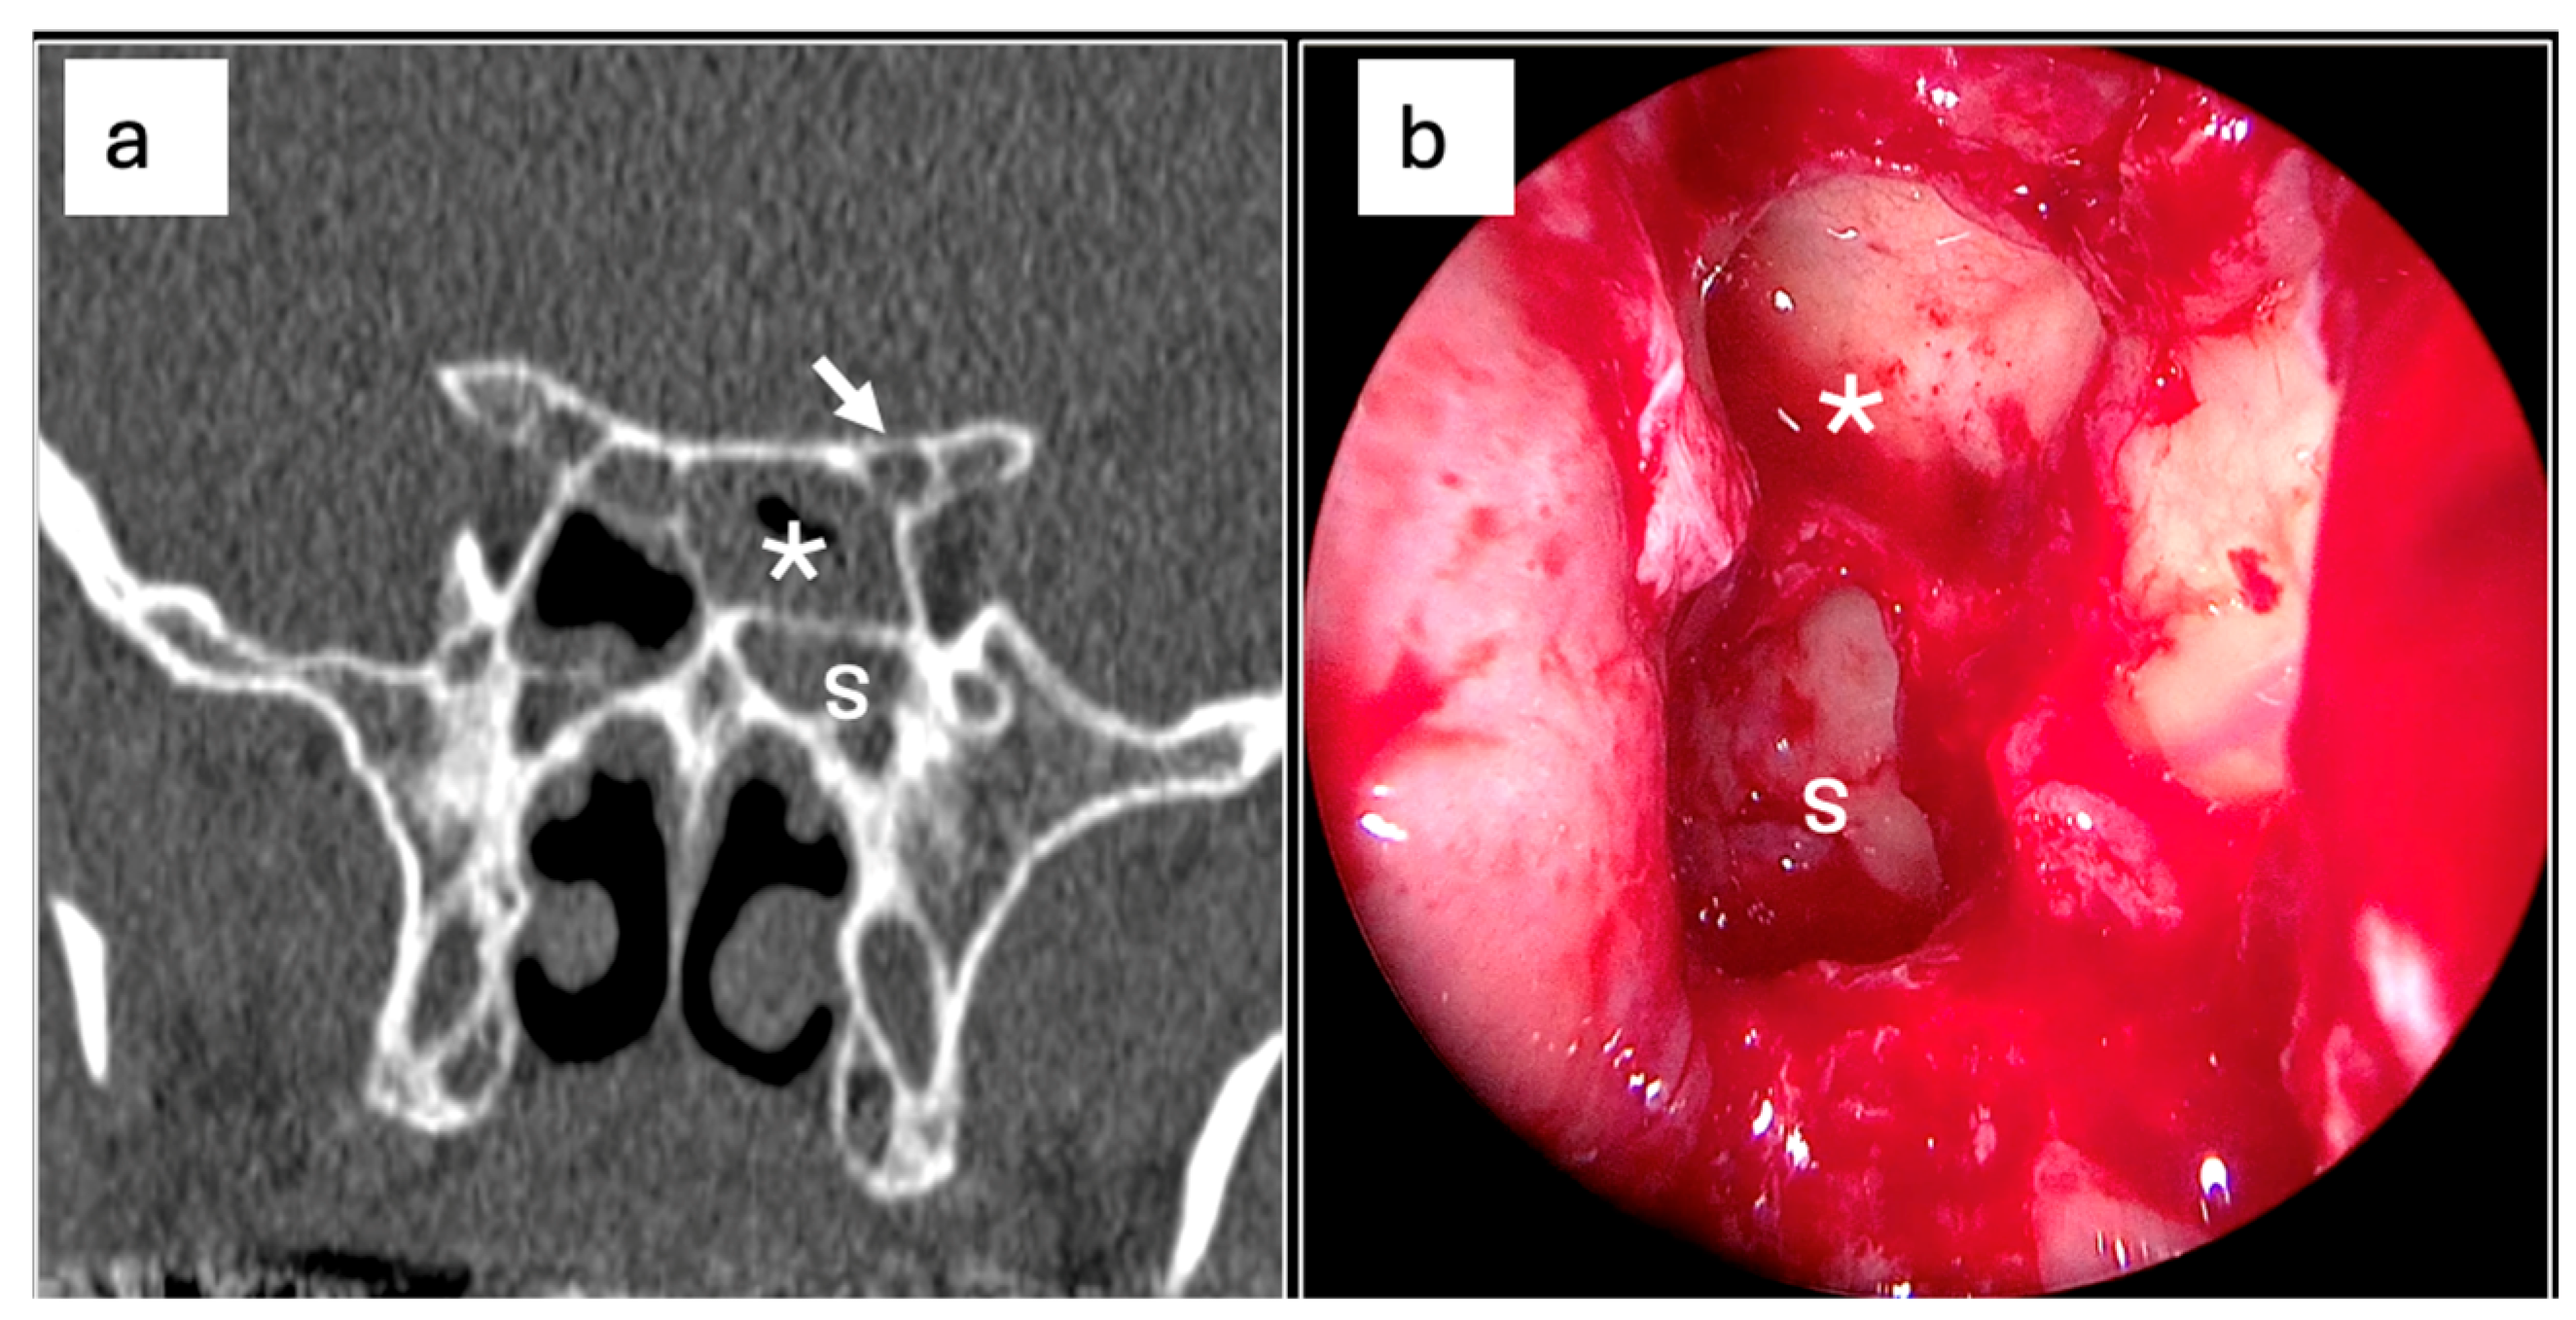

- Fadda, G.L.; Urbanelli, A.; Petrelli, A.; Trossarello, M.; Nitro, L.; Saibene, A.M.; De Corso, E.; Gned, D.; Panfili, M.; Cavallo, G. Type IV optic nerve and Onodi cell: Is there a risk of injury during sphenoid sinus surgery? Acta Otorhinolaryngol. Ital. 2024, 44, 36–41. [Google Scholar] [CrossRef] [PubMed] [PubMed Central]